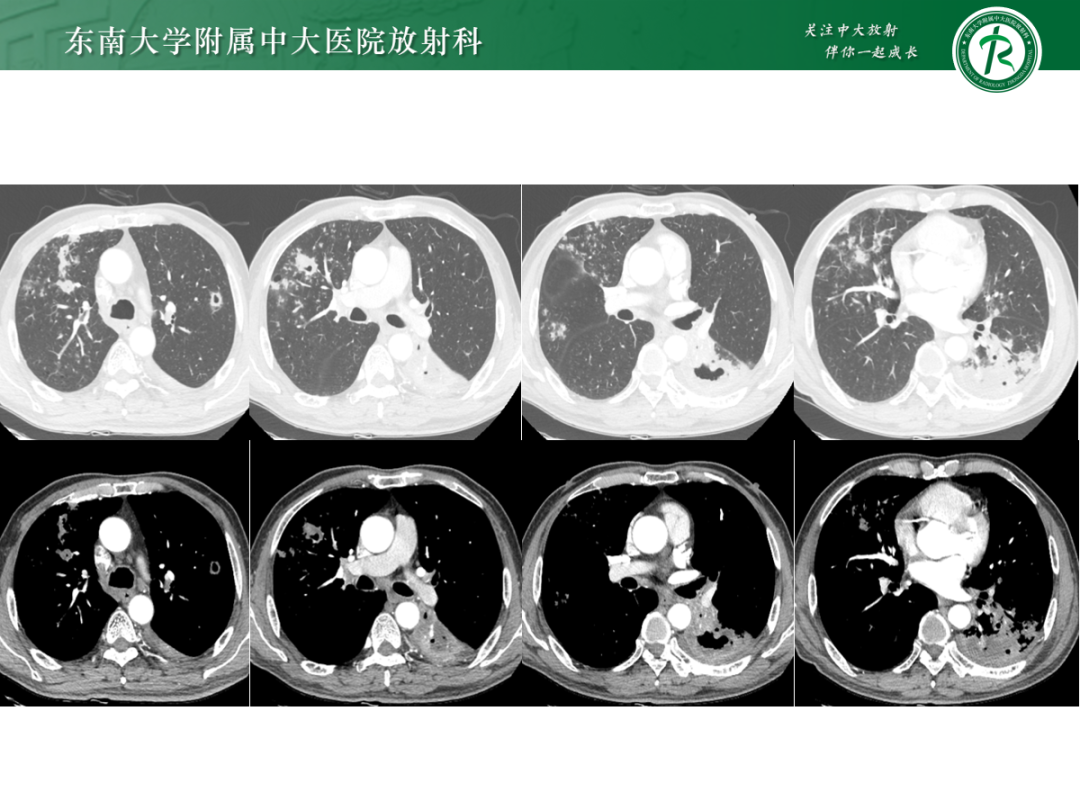

• 病例1:鸟型分枝杆菌复合体肺病

• 病例2:肺诺卡菌病

• 病例3:肺结核

• 病例4:气道侵袭性肺曲霉菌病

影像诊断思路